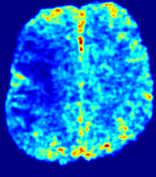

We further simulate noisy concentrations by adding Rician noise [24] with variances equalling 2%, 4%, 6%, 8%, 10% of the originally simulated concentrations {Cti}superscript𝐶subscript𝑡𝑖\{C^{t_{i}}\}. We then test how well PIANO can estimate the underlying velocity field via Eq. 15 with the same model settings (except without estimating the diffusion) as in Sec. 3 given the original and the noisy concentration time-series. Fig. 12 shows the estimated 𝐕est2subscriptnormsuperscript𝐕est2\|{\bf{V}}^{\text{est}}\|_{2} for one patient. Fig. 11 (a) shows the summarized estimation results for all 43 patients. PIANO almost perfectly captures the underlying velocity field, and maintains excellent performance even when estimating from concentrations with varying noise levels.

Figure 12: PIANO effectiveness and robustness testing: advection imaging via advection. Top row shows the ground truth 𝐕gt2subscriptnormsuperscript𝐕gt2\|{\bf{V}}^{\text{gt}}\|_{2} used for simulating pure advection. (a)-(f) refer to the results for 𝐕2subscriptnorm𝐕2\|{\bf{V}}\|_{2} estimated by PIANO, with simulated advection imaging series where Rician noise at levels 0%, 2%, 4%, 6%, 8%, 10% was added respectively.

Slice #1Slice #2Slice #3Slice #4Slice #5Slice #6𝐕gt2subscriptnormsuperscript𝐕gt2\|{\bf{V}}^{\text{gt}}\|_{2}Refer to captionRefer to captionRefer to captionRefer to captionRefer to captionRefer to caption(a)Refer to captionRefer to captionRefer to captionRefer to captionRefer to captionRefer to caption(b)Refer to captionRefer to captionRefer to captionRefer to captionRefer to captionRefer to caption(c)Refer to captionRefer to captionRefer to captionRefer to captionRefer to captionRefer to caption(d)Refer to captionRefer to captionRefer to captionRefer to captionRefer to captionRefer to caption(e)Refer to captionRefer to captionRefer to captionRefer to captionRefer to captionRefer to caption(f)Refer to captionRefer to captionRefer to captionRefer to captionRefer to captionRefer to captionRefer to caption000.30.30.30.60.60.60.90.90.91.21.21.21.51.51.5(mm/s)𝑚𝑚𝑠(mm/s)